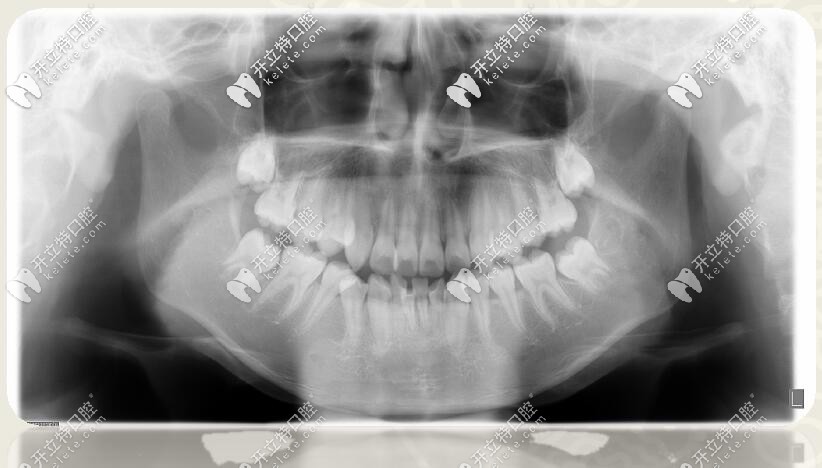

口腔全景片

口腔診斷

診斷

1、安氏Ⅱ類錯(cuò)合

2、骨性二類錯(cuò)合

3、前牙區(qū)深覆蓋、深復(fù)合

4、跨牙合

5、牙列擁擠不齊